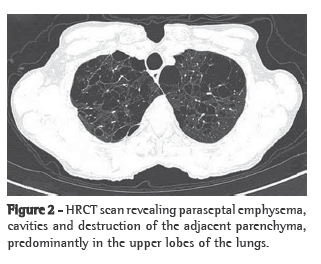

A 69-year-old female smoker (30 pack-years) homemaker from São Sepe, Brazil, presented with rheumatoid arthritis for 14 years. The patient had undergone a thyroidectomy 20 years before. The epidemiological history was not clear regarding possible fungal exposure. The patient had been experiencing progressive dyspnea, productive cough, recurrent respiratory infections, loss of appetite, nausea and weight loss for 4 years. The patient was using levothyroxine, calcitriol and prednisone 15 mg/day; however, she had previously used methotrexate. Physical examination revealed that the patient had lost weight (patient weight at the time was 30 kg, and body mass index was 14 kg/m2). No cervical lymph node enlargement, supraclavicular lymph node enlargement or digital clubbing was observed. Pulmonary auscultation revealed only a diffuse reduction in breath sounds. A chest X-ray taken at the onset of the condition (4 years before) showed lung hyperinflation and severely decreased vascular markings in the upper halves of both lung fields (Figure 1). An HRCT scan had revealed paraseptal emphysema, cavities and destruction of the lung parenchyma, predominantly in the upper lobes (Figure 2). Arterial blood gas analysis and the tuberculin skin test revealed no abnormalities.